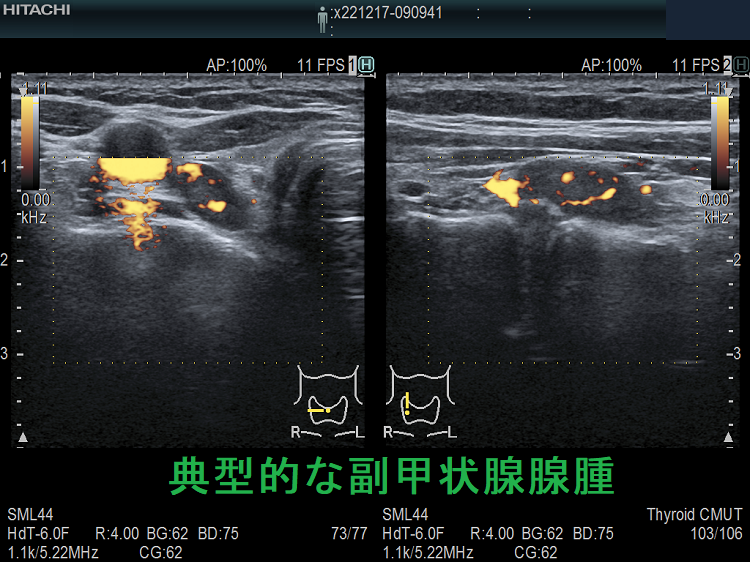

(➸)原因となる副甲状腺腺腫、副甲状腺癌、副甲状腺過形成をデジタルハイビジョン超音波診断装置で診断。エコーでは、甲状腺とのインピーダンスの違いにより、甲状腺-副甲状腺境界部に線状高エコーが生じます(右図の↓)。内部は中心血流を認め、リンパ節でないのが分かります。

ケース①

ケース② 右腕頭動脈分岐部上の副甲状腺腫

ケース②